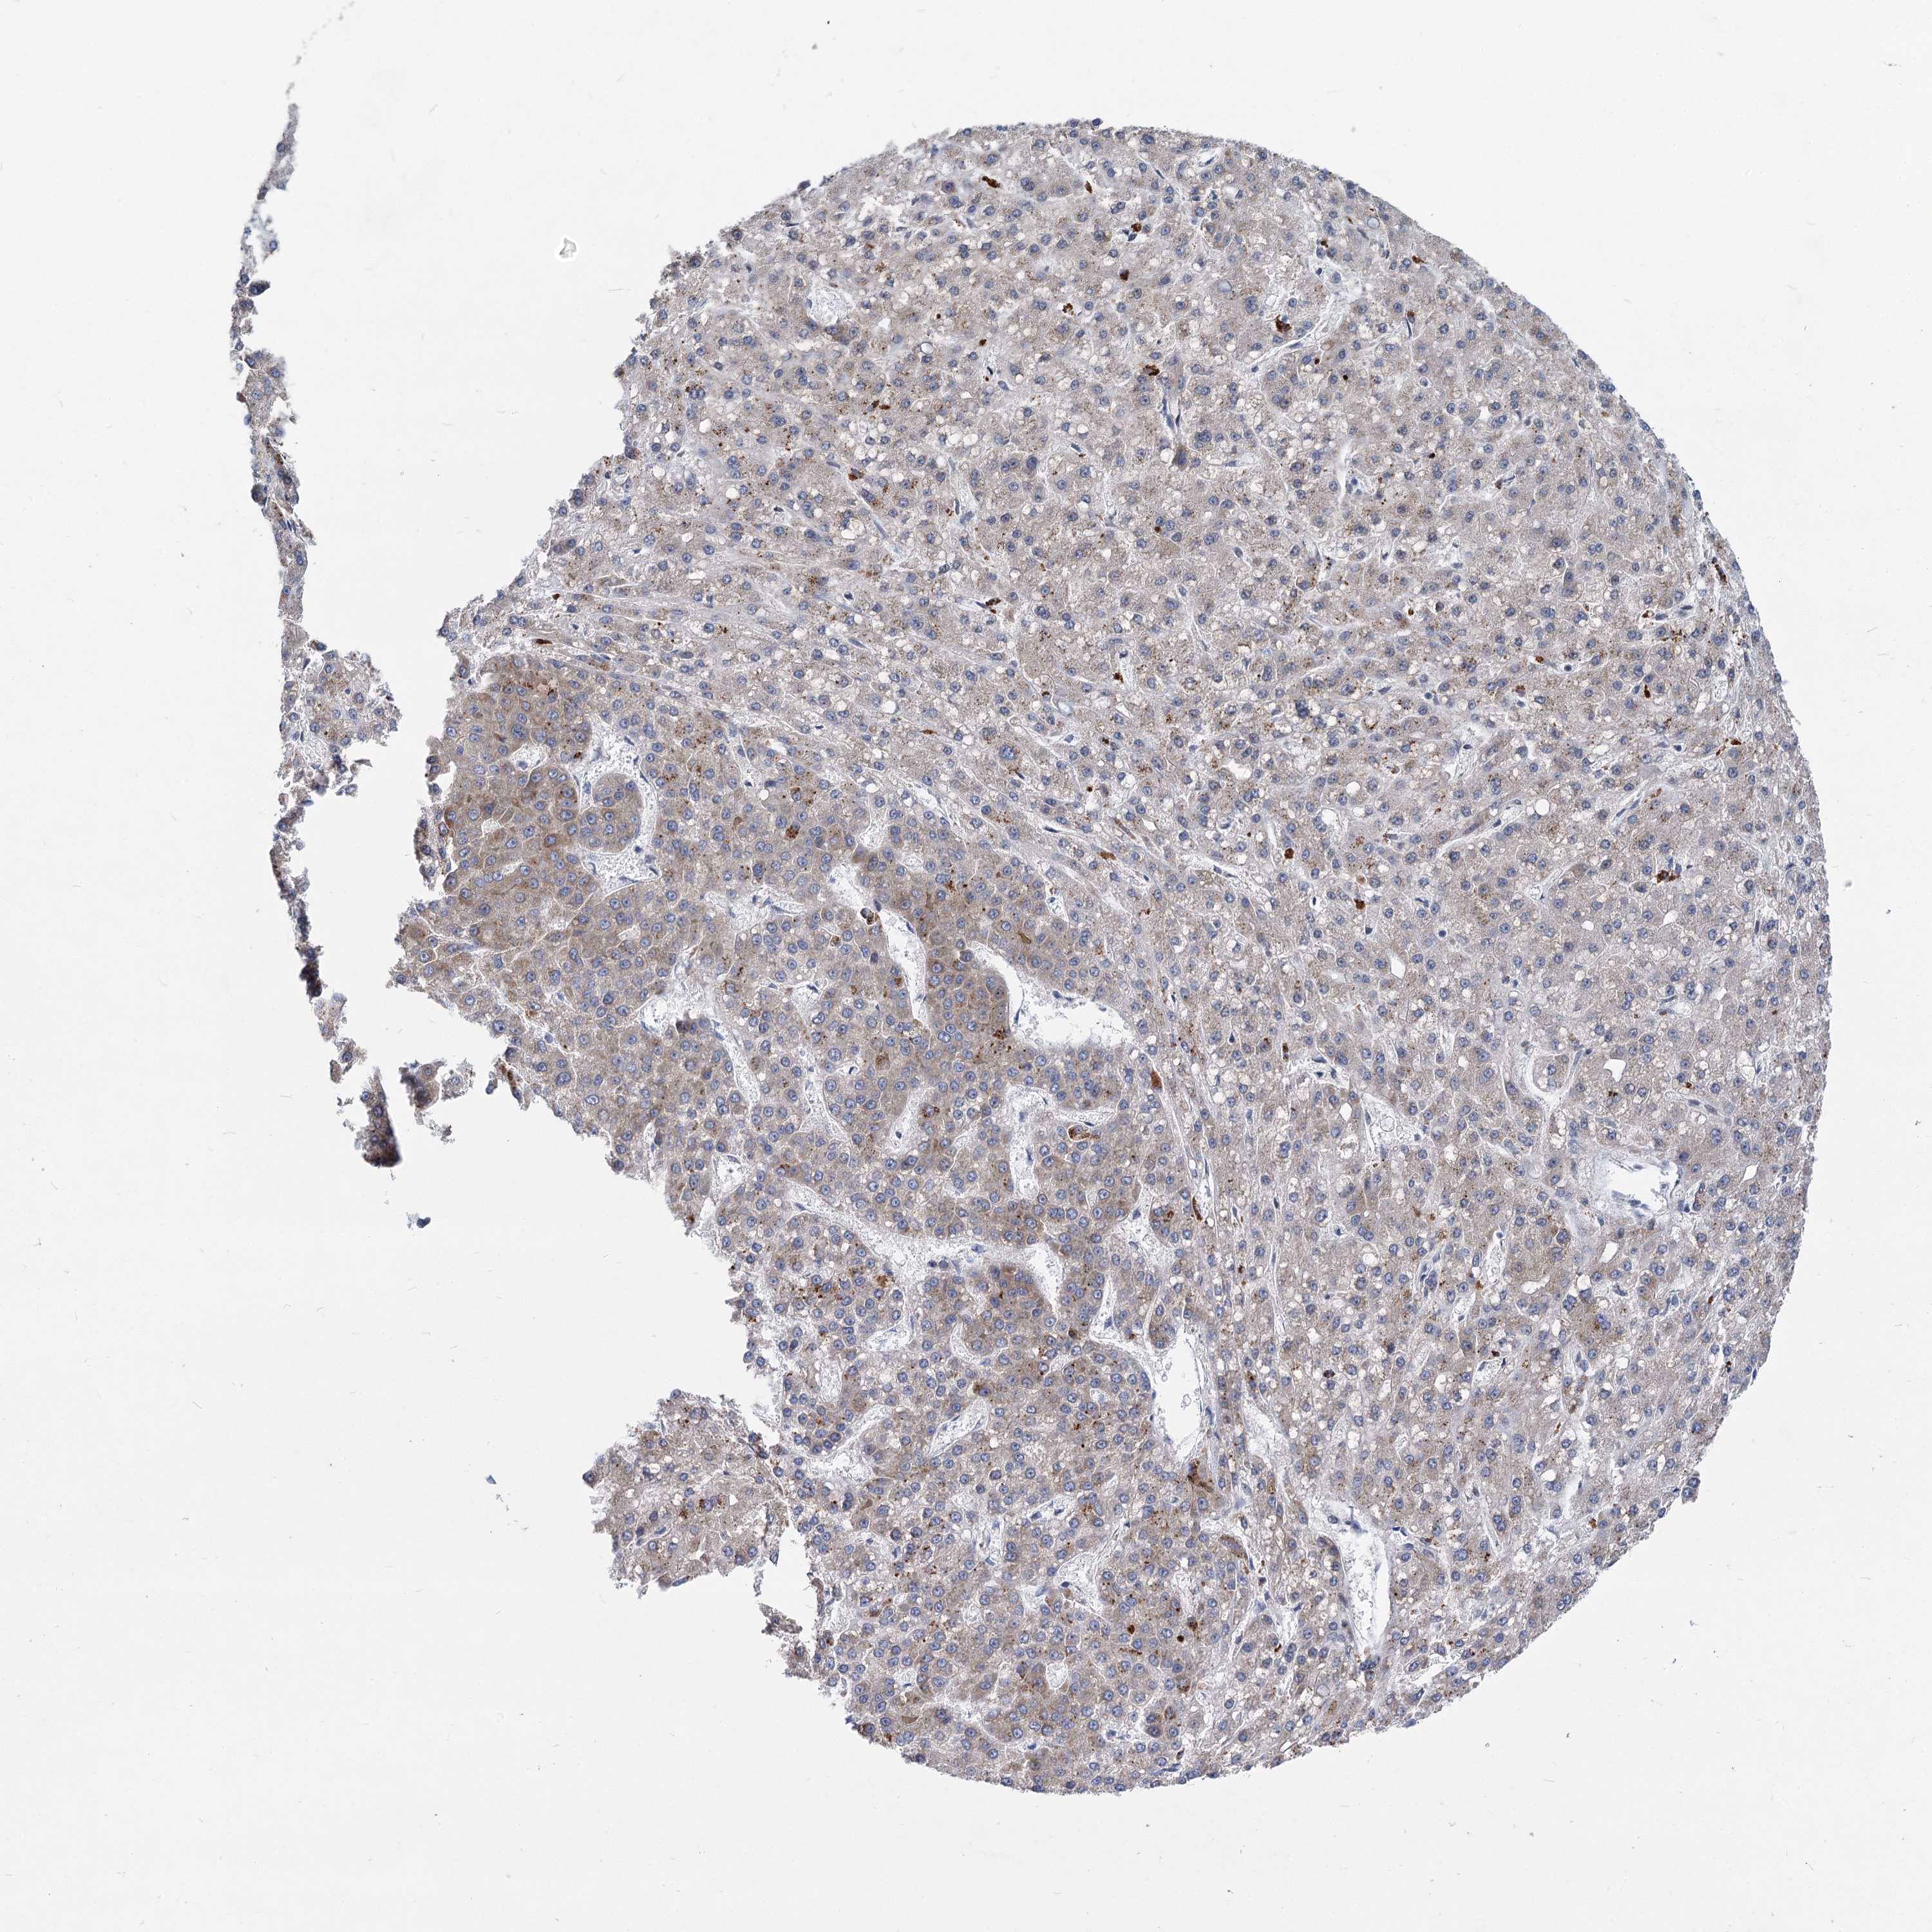

LIVER CANCER - Protein expressioni

A mouse-over function shows sample information and annotation data. Click on an image to view it in a full screen mode. Samples can be filtered based on level of antibody staining by selecting one or several of the following categories: high, medium, low and not detected. The assay and annotation is described here.

Antibody stainingi

Antibody staining in the annotated cell types in the current human tissue is reported as not detected, low, medium, or high, based on conventional immunohistochemistry profiling in selected tissues. This score is based on the combination of the staining intensity and fraction of stained cells.

Each image is clickable and will lead to virtual microscopy that enables deeper exploration of all samples and also displays staining intensity scores, fraction scores and subcellular localization as well as patient and tissue information for each sample.

Antibody HPA036633

Antibody HPA058130

Staining

High

Medium

Low

Not detected

Intensity

Strong

Moderate

Weak

Negative

Quantity

>75%

75%-25%

<25%

None

Location

Nuclear

Cytoplasmic/membranous

Cytoplasmic/membranous,nuclear

Cholangiocarcinoma

Carcinoma, Hepatocellular, NOS